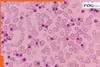

Discover various factors that can lead to heart skip a beat, ranging from benign triggers like caffeine and stress to more serious underlying conditions. Learn about the symptoms, risk factors, and when to seek medical attention for this sensation of a racing or irregular heartbeat.

Heart Problems: Discover various factors that can lead to heart skip a beat, ranging from benign triggers like caffeine and stress to more serious underlying conditions. Learn about the symptoms, risk factors, and when to seek medical attention for this sensation of a racing or irregular heartbeat.